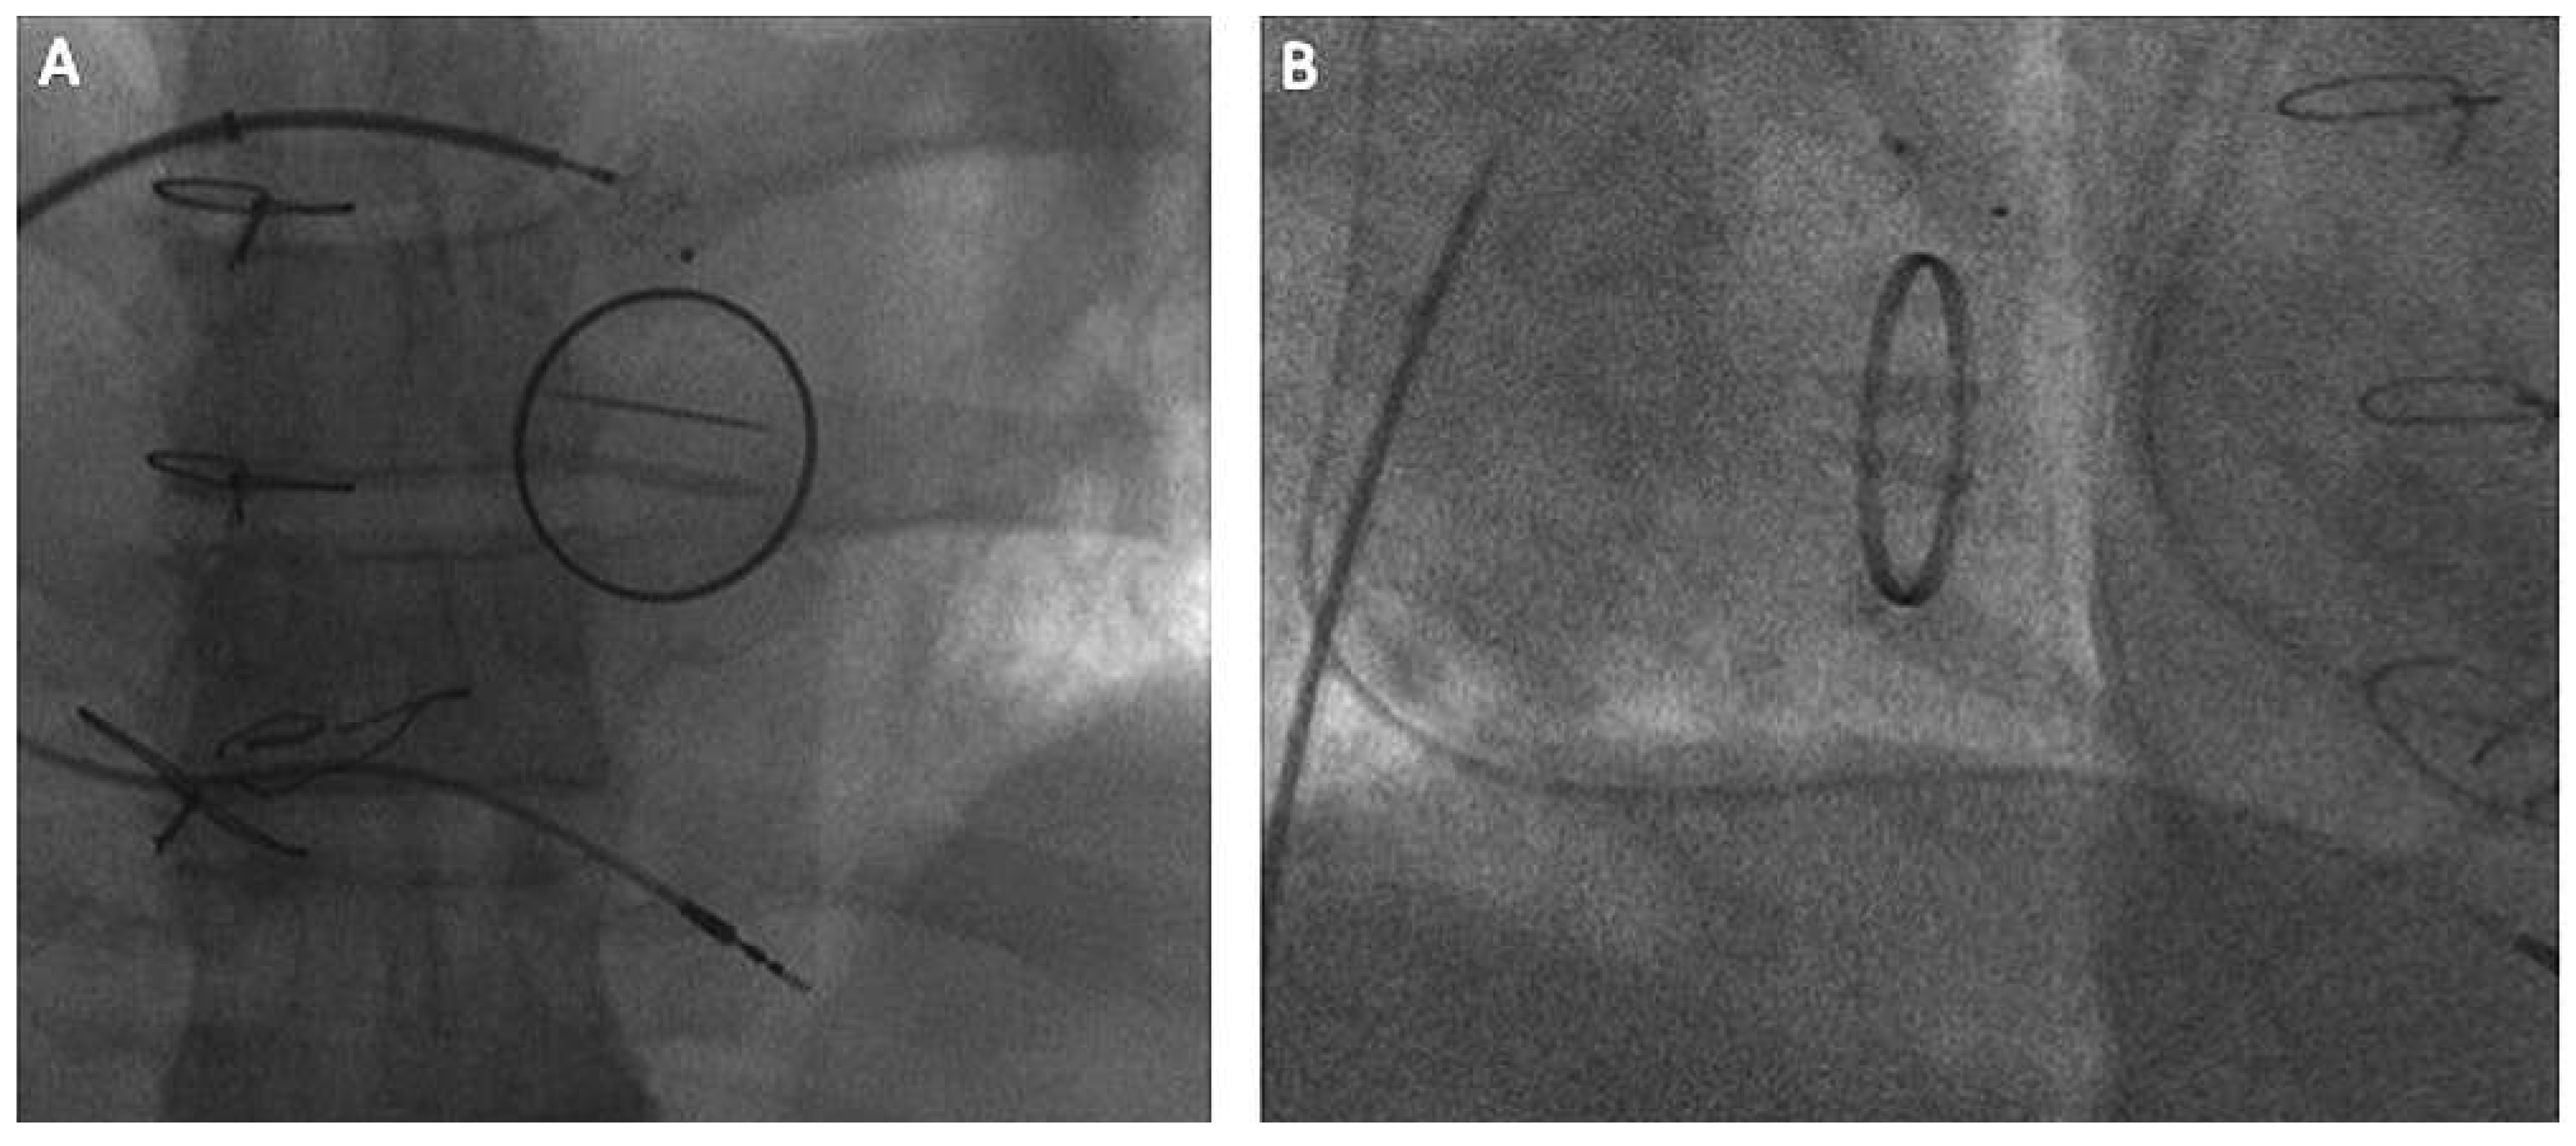

Considerations for mitral paravalvular leak

Alternative approach